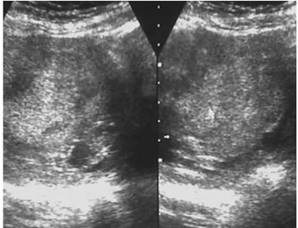

Los estudios complementarios solicitados a nivel sanguíneo demostraron varias alteraciones (tabla 2). Entre las que se destacan una disminución de los niveles séricos de hemoglobina y plaquetas; con un aumento de las cifras sanguíneas de fracción beta de gonadotropina coriónica humana (BHCG). Además, hubo otros hallazgos en las pruebas de sangre que son característicos por representar un factor de riesgo para el desarrollo de esta patología (tabla 3). A nivel ecográfico se observó quistes tecaluteínicos en ovario derecho más imágenes en tormenta de nieve (figura 1 y 2).

Figura 1: Imagen en tormenta de nieve característica de una enfermedad trofoblástica. Fuente: Historia clínica.